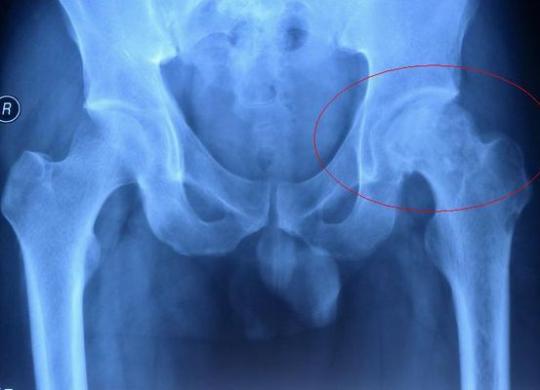

股骨头缺血性坏死是由于多种原因导致的股骨头局部血运不良,…… 【详情】

股骨头缺血性坏死患者去医院看病时,对于医生建议做X线、CT或…… 【详情】